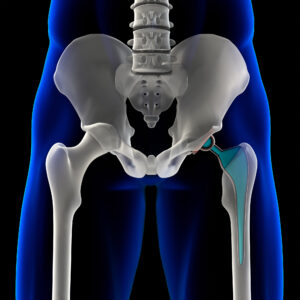

The procedure replaces damaged and diseased cartilage and bone from the hip joint with an artificial joint. This is made up of two components: the femoral prosthesis which replaces the ball or femoral head, and the acetabular prosthesis which replaces the socket or acetabulum.

Representative image of THR.